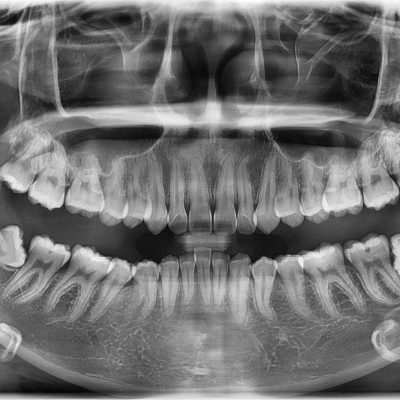

#18,28,38,48 사랑니 발치 #18,28,38,48 사랑니 발치 구강 외과 전문의가 당일 발치했습니다. --------------------..

작성자 이턱이 작성일 01-29 조회 9